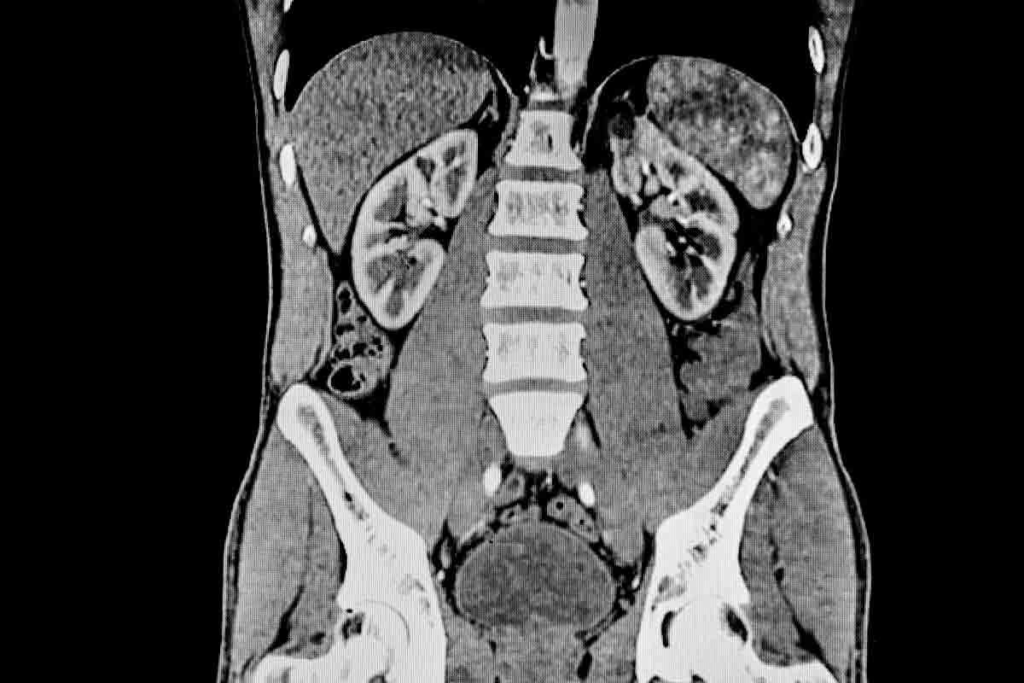

Renal CT scans are key in spotting many kidney issues. CT scans of the kidneys give detailed pictures. These help doctors diagnose and treat kidney diseases.

Kidney CT scans find many problems, like renal stones, tumors, infections, and cysts. They’re great for spotting kidney stones. These can cause a lot of pain and serious issues if not treated right away.

CT scans help doctors plan the best treatment. For example, they can show how big and where kidney stones are. This helps decide if surgery is needed.

Knowing how renal CT scans work helps patients understand their health better. With the detailed images from CT scans, doctors can give more precise and effective care.